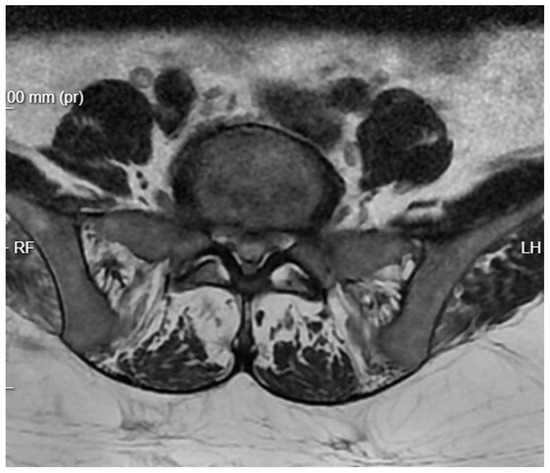

Diagnostic Evolution: After a week of conservative treatment without improvement, a follow-up MRI was ordered(Figure 3), which unambiguously identified spondylodiscitis with an abscess in the canal, causing compression of the dural sac and both S1 nerves (Figure 4). The patient’s pain syndrome worsened significantly, VAS 9 in the lower spine, leading to her qualification for surgical treatment.

Figure 4. Pre-operative T2 axial MRI image at the L5/S1 level one week after admission to the neurology department.